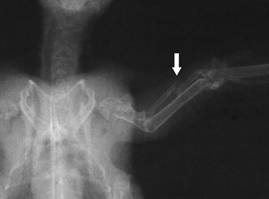

Patient after the

operation: Internal fixation of a broken radius with an

intramedullary pin (IM pin, arrow: nail exit). Photo: C. Haupt

Radius fracture,

dislocated  |

Radius fracture

after intramedullary pinning with a 0.4 mm

The relatively frequent

radius fracture, which, if not treated, can lead to limited flight

ability, is pinned by using a 0.4 mm cannula, which is inserted into

the distal end of the fracture, exits through the radius head which

is palpable at the shoulder joint and is retrogradely pushed into

the proximal end of the fracture as far as just in front of the

elbow joint. The pin coming out at the shoulder joint is released 1

- 2 mm over the skin, and is protected with a small adhesive strip,